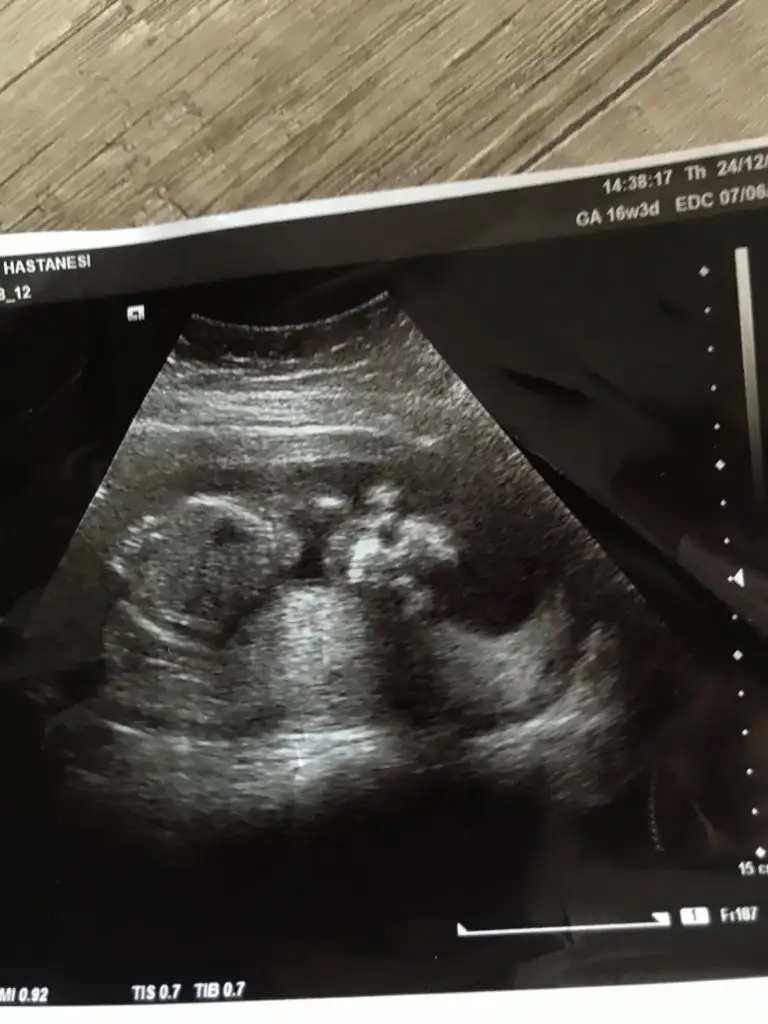

Cinsiyet

Hmmö şimdi anladım cnm peki ne dıyosun kızçe mi 🙄🥰

Kalça tarafı daha yuvarlak gibi geldi o yüzden kız dedim ama tabii daha çok küçük

Canm birde buna bakar mısın teyzesi 17 haftalık olduk doktor erkek gibi çıkıntısı var ama göbek kordonu izasında dedıedaya bakar mısın

Ben goremedım cnm nerde çıkıntı var cinsiyet organı belli mi bu üst fotoda

Hayır canım organdan değil çıkıntılar erkeklerde daha dik kız bebeklerde daha oval oluyor. Bende sağlıkçı değilim gördüğüm ultrasonlardan yola çıkarak tahmin sadece